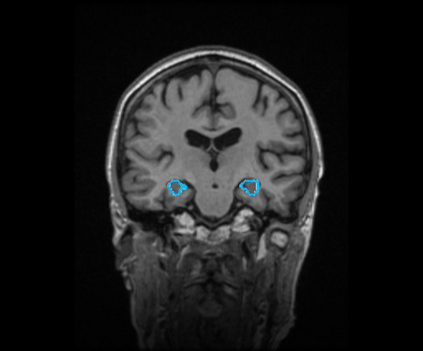

Radiomics uses quantitative medical imaging features to predict clinical outcomes. Currently, in a new clinical application, finding the optimal radiomics method out of the wide range of available options has to be done manually through a heuristic trial-and-error process. In this study we propose a framework for automatically optimizing the construction of radiomics workflows per application. To this end, we formulate radiomics as a modular workflow and include a large collection of common algorithms for each component. To optimize the workflow per application, we employ automated machine learning using a random search and ensembling. We evaluate our method in twelve different clinical applications, resulting in the following area under the curves: 1) liposarcoma (0.83); 2) desmoid-type fibromatosis (0.82); 3) primary liver tumors (0.80); 4) gastrointestinal stromal tumors (0.77); 5) colorectal liver metastases (0.61); 6) melanoma metastases (0.45); 7) hepatocellular carcinoma (0.75); 8) mesenteric fibrosis (0.80); 9) prostate cancer (0.72); 10) glioma (0.71); 11) Alzheimer's disease (0.87); and 12) head and neck cancer (0.84). We show that our framework has a competitive performance compared human experts, outperforms a radiomics baseline, and performs similar or superior to Bayesian optimization and more advanced ensemble approaches. Concluding, our method fully automatically optimizes the construction of radiomics workflows, thereby streamlining the search for radiomics biomarkers in new applications. To facilitate reproducibility and future research, we publicly release six datasets, the software implementation of our framework, and the code to reproduce this study.

翻译:放射科使用定量医学成像特征来预测临床结果。目前,在一个新的临床应用中,通过一个超常试验和高压过程,通过人工操作,从广泛的现有选项中找到最佳放射法。在本研究中,我们提议了一个框架,自动优化每个应用程序的放射工作流程的建设。为此,我们将放射作为模块工作流程,并包括每个部件的大量通用算法。为了优化每个应用程序的工作流程,我们使用随机搜索和聚合的自动机学习方法。我们用12种不同的临床应用来评估我们的方法,结果在曲线下应用的以下领域:1) 脂色瘤(0.83);2) 脱氧型纤维瘤(0.82);3 初级肝脏肿瘤(0.80);4 气肠肿瘤(0.77)、5 彩虹肝脏移植(0.61); 6 脑膜细胞变异常(0.45); 7) 肝细胞变异常(0.8) 脑纤维变异位(0.80); 9) 直径直线型癌症(0.74) 和头型癌症(0.77) 直径研究(10) 。